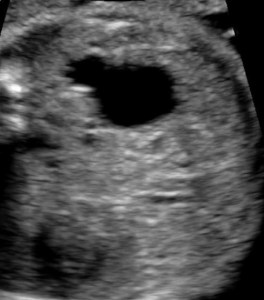

Ureteropelvic junction obstruction.

Calyceal distention is best imaged in the sagittal plane.